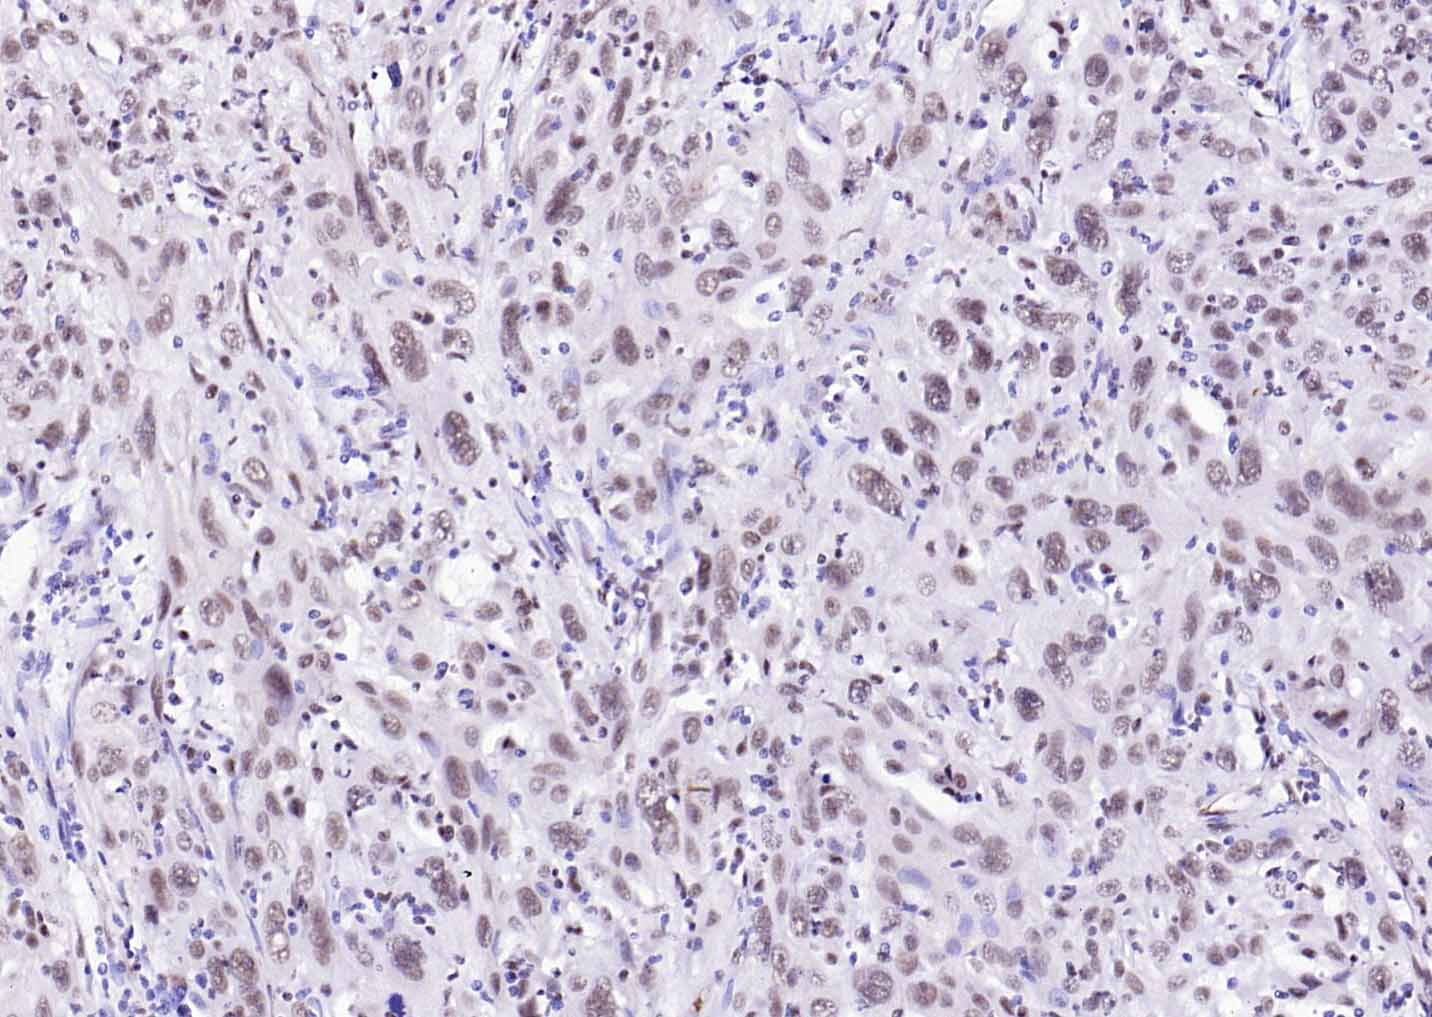

Paraformaldehyde-fixed, paraffin embedded Human Cervical Cancer; Antigen retrieval by boiling in sodium citrate buffer (pH6.0) for 15 min; Antibody incubation with ESR2 Polyclonal Antibody, Unconjugated (bs-0116R) at 1:200 overnight at 4°C, followed by conjugation to the SP Kit (Rabbit, SP-0023) and DAB (C-0010) staining.

Paraformaldehyde-fixed, paraffin embedded Mouse Cerebrum; Antigen retrieval by boiling in sodium citrate buffer (pH6.0) for 15 min; Antibody incubation with ESR2 Polyclonal Antibody, Unconjugated (bs-0116R) at 1:200 overnight at 4°C, followed by conjugation to the SP Kit (Rabbit, SP-0023) and DAB (C-0010) staining.

Paraformaldehyde-fixed, paraffin embedded Rat Cerebrum; Antigen retrieval by boiling in sodium citrate buffer (pH6.0) for 15 min; Antibody incubation with ESR2 Polyclonal Antibody, Unconjugated (bs-0116R) at 1:200 overnight at 4°C, followed by conjugation to the SP Kit (Rabbit, SP-0023) and DAB (C-0010) staining.